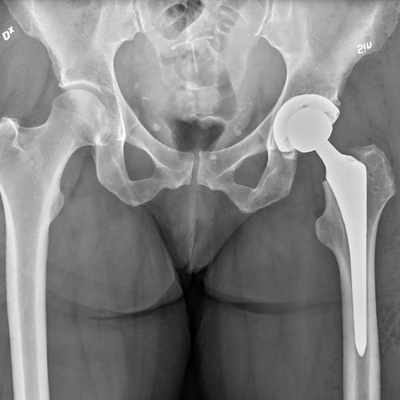

Click on an image below to view more info.